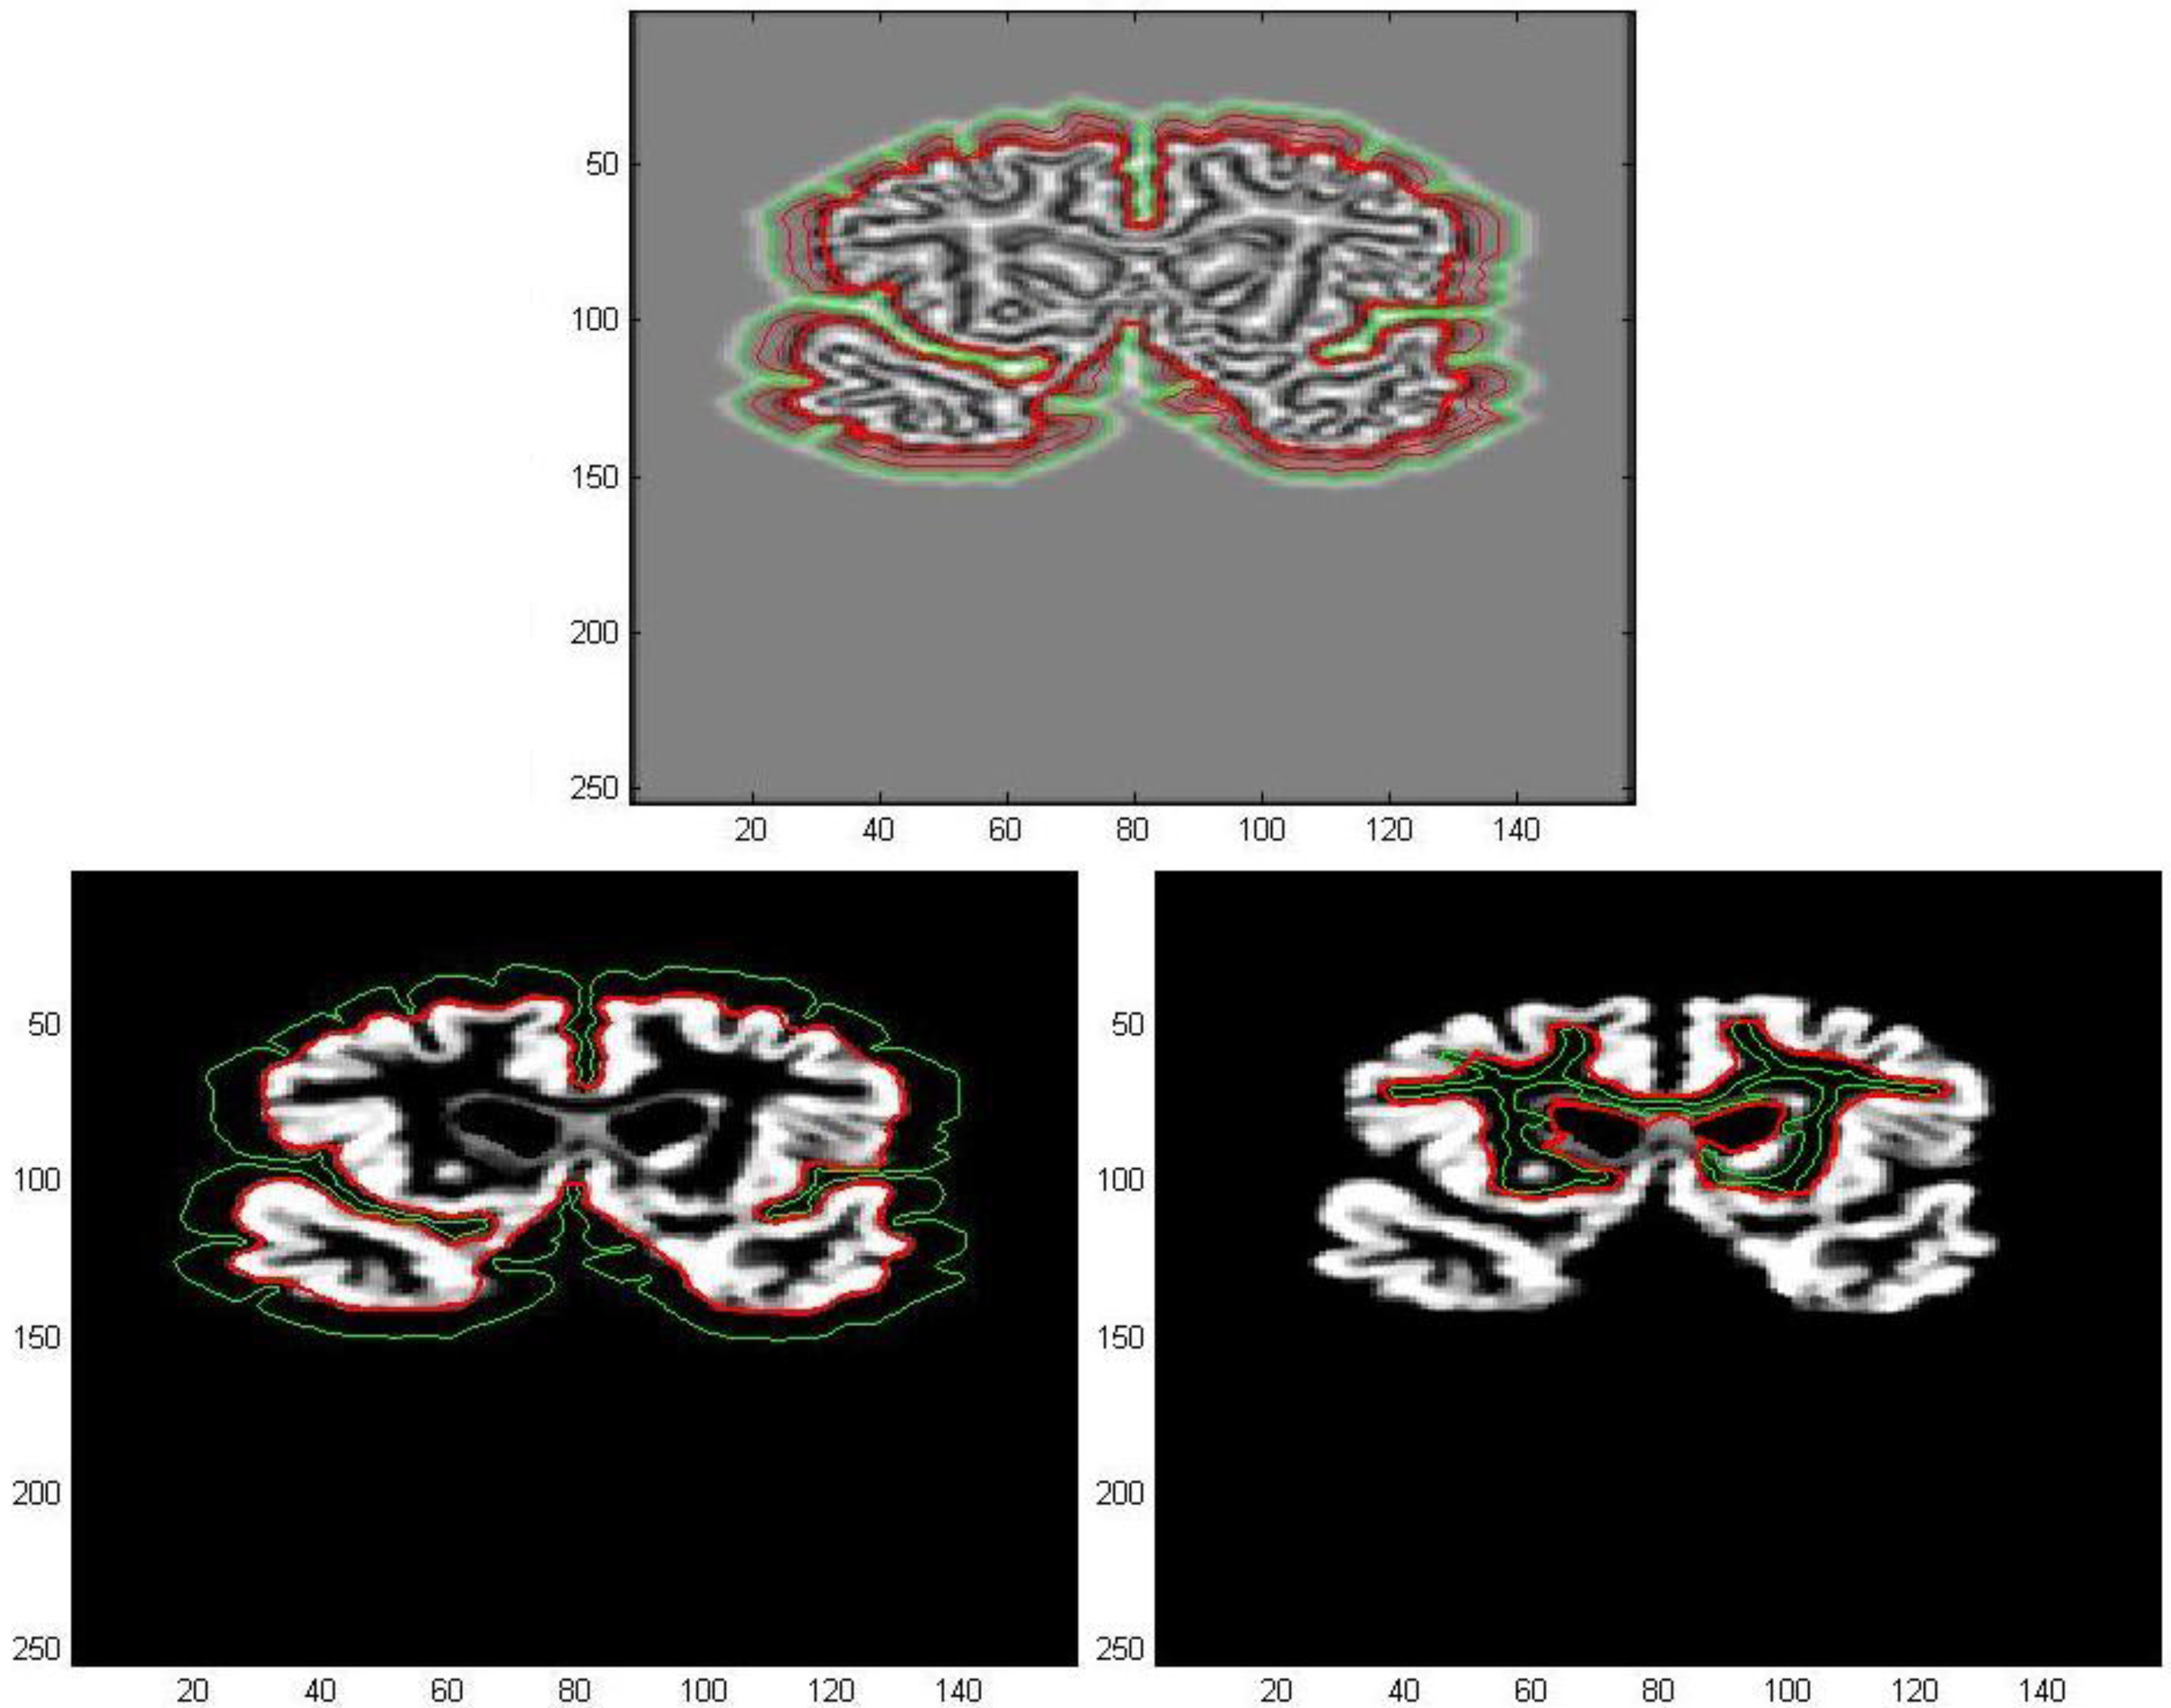

The first processed GM image (Figure 11) refers to a subject of the control group (see the first image of Figure 12). The force field has been evaluated from Equation (9) after eight iterations, the overlapping green curves represent initial contours that are automatically selected from the contour map of divergence. In Figure 13 and Figure 14 we have treated GM images derived from two patients affected by Alzheimer’s disease and they refer respectively to the second and third images which are shown in Figure 12. Once edges are detected, we produce a boundary representation of gray matter that can be used for an automatic analysis of shapes from the geometrical, metrical or morphological point of view.

Figure 11. Edge extraction with AVF force field after 8 iterations.

Algorithms 05 00636 g011